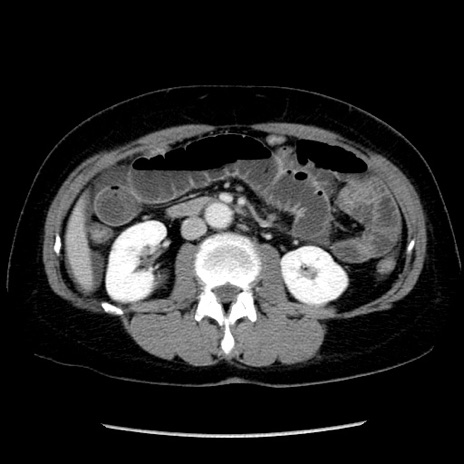

症例6(横断像)

【症例】50歳代女性

【既往歴】卵巣癌術後(8年前に当院で卵巣摘出)

【身体所見】 意識清明、腹部:平坦、腸蠕動音→、やや硬、下腹部自発痛・圧痛あり、反跳痛あり、筋性防御なし。

【データ】WBC 16000、CRP 0.01